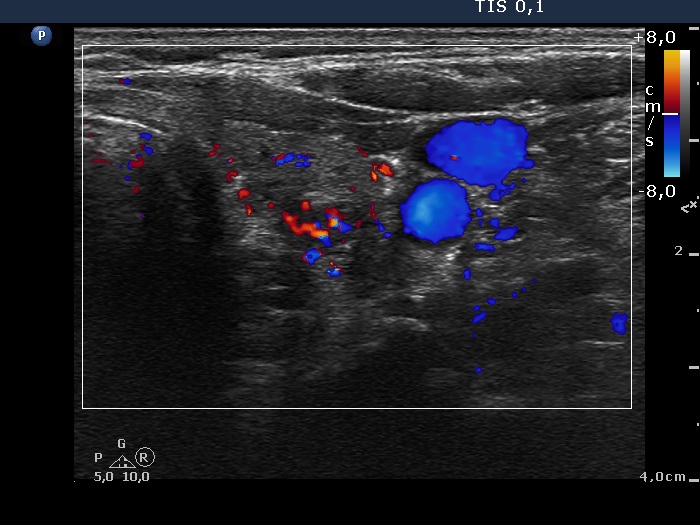

Ultrasonography. The thyroid was echonormal. There were multiple moderately hypoechogenic nodules in the right lobe making the appearance micronodular. There was a relatively larger hyperechogenic nodule in the isthmus. The left lobe contained a hypoechogenic lesion, which presented blurred borders, microcalcifications and an increase intranodular blood flow.